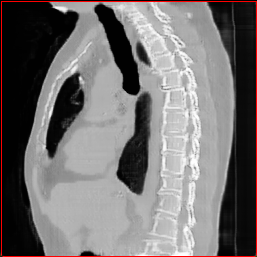

HA-GAN (sun2022hierarchical)

GenerateCT (hamamci2024generatect)

MedSyn (xu2024medsyn)

MAISI-DDPM (guo2025maisi)

MAISI-v2

Figure 2: Qualitative comparison across axial (top row), sagittal (middle row), and coronal (bottom row) views. Columns correspond to different methods. MAISI-DDPM and MAISI-v2 in this figure are unconditional synthesis which do not use ControlNet or segmentation maps.

Qualitative Evaluation:

Figure 2 presents representative slices from the axial, sagittal, and coronal planes. GenerateCT (hamamci2024generatect) is a 2D model, so it lacks inter-slice consistency, leading to poor image quality in the sagittal and coronal views. MedSyn (xu2024medsyn) produces noticeably blurry results with mosaic-like artifacts, such as region inside the red box. HA-GAN (sun2022hierarchical) generates visually sharp images but with mosaic-like artifacts, such as region inside the red box. Also, its voxel spacing is not available, which limits its applicability in real-world medical imaging tasks. Moreover, all three methods are restricted to synthesizing small anatomical regions. In contrast, both MAISI and MAISI-v2 are capable of generating high-quality 3D volumes that span larger body regions while preserving fine anatomical details and realistic structure.